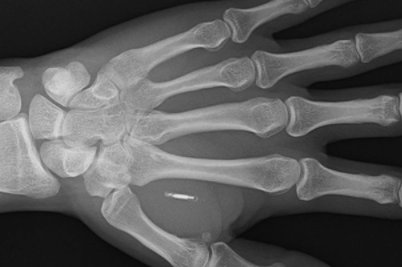

Biohacker非接触式支付芯片生物黑客PatrickPaumen最近在他不断增长的一系列增强功能中添加了一个新的微芯片植入物,现在总共有32个生物植入物,其中现在包括一个非接触式支付芯片,让他无需使用智能手机或钱包即可轻松方便地支付物品.

”Paumen先生将自己描述为一个“生物黑客”——将一些技术植入自己的身体以试图提高自己的表现的人。他总共有32个植入物,包括用于开门的芯片和嵌入的磁铁”——“技术不断发展,所以我不断收集更多,”他说。“我的植入物增强了我的身体。我不想没有他们,”他说。”–“总会有人不想改变自己的身体。我们应该尊重这一点——他们应该尊重我们作为生物黑客”,BBC网站写道。

“这是因为这位37岁的老人不需要使用银行卡或手机支付。相反,他只需将左手放在非接触式读卡器附近,即可完成付款。“我从收银员那里得到的反应是无价的!”来自荷兰的保安Paumen先生说。他能够用手支付,因为早在2019年,他的皮肤下就注射了一个非接触式支付微芯片。“这个过程就像有人捏你的皮肤一样疼,”波门先生说。